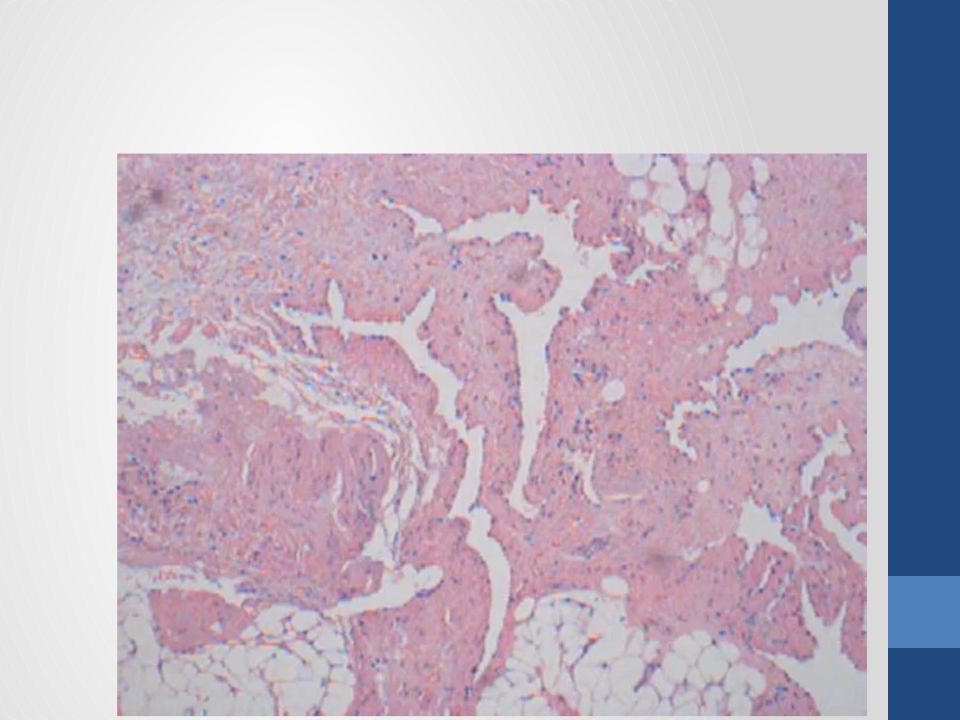

- •Гистологическая картина

- •Липома микропрепарат